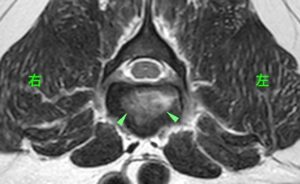

MRI検査で腰の背骨と椎間板に白い領域がみられ(黄緑矢頭)、炎症が疑われた。

さらにこの病変部は造影剤によって、より白く染まったことから椎間板脊椎炎が疑われる。